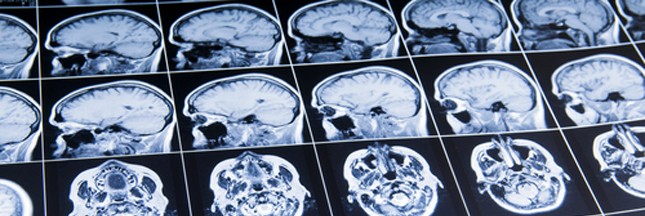

La prise en charge s’est également améliorée dans les hôpitaux : la France s’est progressivement dotée d’une politique de santé spécifique et s’est pourvue, au sein des hôpitaux, d’unités neuro-vasculaires dédiées à la prise en charge des AVC. Une chose est sûre, la sensibilité croissante des techniques d’imagerie cérébrale et un meilleur maillage territorial de ces unités neuro-vasculaires, a été grandement favorable pour les patients.

Illustration bannière © Ahuli Labutin – Shutterstock